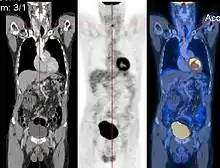

Registration

Image registration is a process that searches for the correct alignment of images.[14][15][16][17] In the simplest case, two images are aligned. Typically, one image is treated as the target image and the other is treated as a source image; the source image is transformed to match the target image. The optimization procedure updates the transformation of the source image based on a similarity value that evaluates the current quality of the alignment. This iterative procedure is repeated until a (local) optimum is found. An example is the registration of CT and PET images to combine structural and metabolic information (see figure).

- Combining complementary information from different imaging modalities. An example is the fusion of anatomical and functional information. Since the size and shape of structures vary across modalities, it is more challenging to evaluate the alignment quality. This has led to the use of similarity measures such as mutual information.[18]